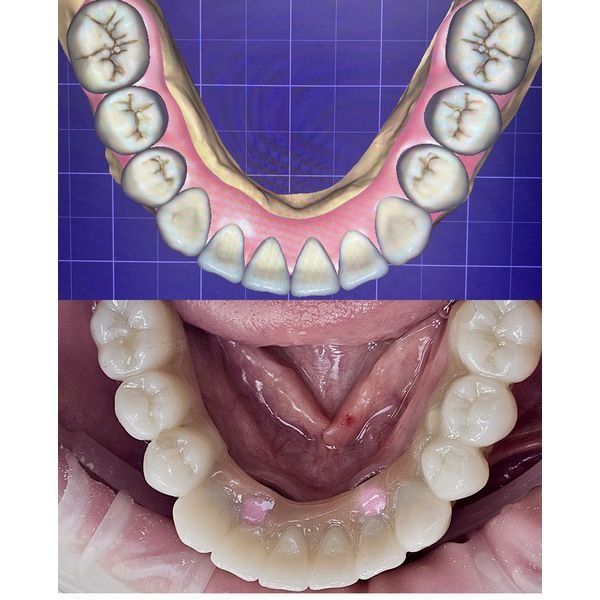

- Установили 6 имплантатов на нижней челюсти с использованием навигационного хирургического шаблона. На период приживления имплантатов изготовили временный акриловый протез с опорой на эти имплантаты. Продолжительность второго этапа — 4 месяца.

- Выполнили постоянное протезирование с использованием мультиюнитов (переходных элементов для фиксации протезов). Изготовили несъёмный цельноциркониевый протез, армированный титановой балкой. Этот материал является самым эстетичным и износостойким.

В итоге полностью восстановили жевание и речь, достигли нужного эстетического результата.